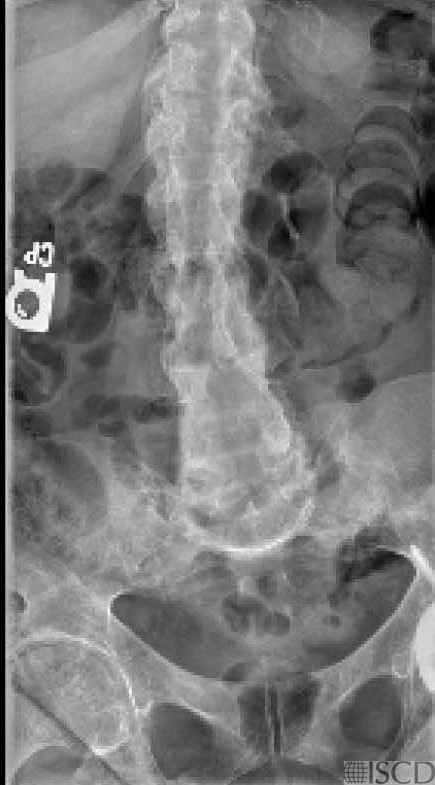

The lumbar spine radiograph show enthesopathic abnormalities characteristic of hypophosphatemic rickets. There is a laminectomy. There are diffuse DISH-like changes and bony remodeling with generalized osteopenia consistent with the hypophosphatemic rickets.

The spine is not scanned because of laminectomy and spinal fusion. The patient was not able to internally rotate the hip, and the femoral neck region of interest includes a portion of the femoral head. Patients with hypophosphatemic rickets have low bone mineral density. The radiographic findings characteristic of hypophosphatemic rickets are like nutritional rickets and can include metaphyseal margins that are indistinct, widening of metaphyseal ends, cupping, and metaphysis concavity. Patients may have bowed legs and knock knees and thickened wrists and ankles. Enthesopathic abnormalities are frequently seen in the pelvis and spine.